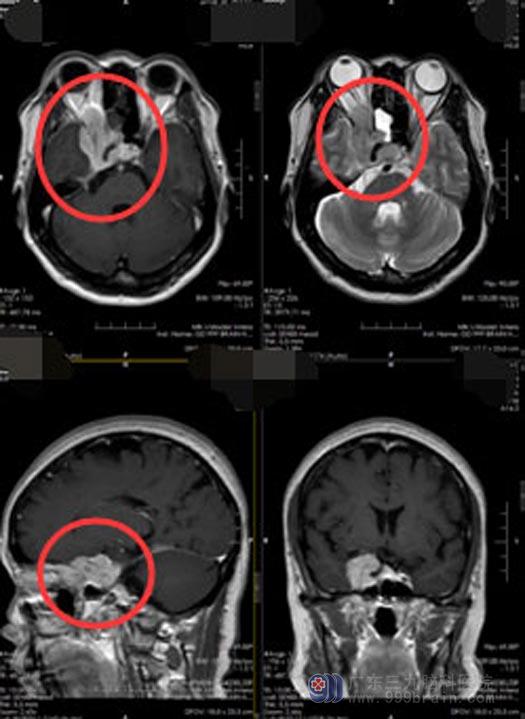

入院后进一步头颅MR检查显示:右侧鞍旁海绵窦区占位性病变,包绕右侧颈内动脉,凸入鞍内、蝶窦及右侧眼眶,压迫右侧视神经,考虑脑膜瘤可能性大。

肿瘤范围约4.3×3.7×2.6cm,且质地坚韧,肿瘤包饶颈内动脉,如要全切肿瘤,有可能会损伤到颈内动脉,术前行脑血管造影及Allen实验(检查手部的血液供应,桡动脉与尺动脉之间的吻合情况)评估。患者颅内前、后侧枝循环代偿差,Allen实验阴性,桡动脉与尺动脉侧枝循环好,准备行颅内外血管搭桥。